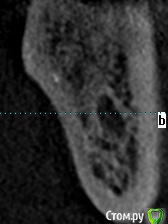

meld Опубликовано 7 ноября, 2017 Автор Поделиться Опубликовано 7 ноября, 2017 Прицельный снимок 38 зуба и его срезы Ссылка на комментарий